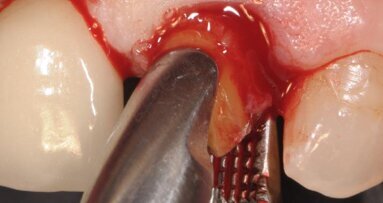

Il poter disporre di una tipologia di fixture estremamente orientata al conseguimento di elevati valori di stabilità primaria ha costituito un ulteriore elemento a favore di questa scelta. La paziente è stata sottoposta ad un trattamento preliminare a cielo coperto mediante levigatura radicolare. Il giorno dell’intervento, sotto profilassi antibiotica, è stata eseguita l’estrazione in maniera micro-traumatica e la rimozione mediante curettage dei tessuti infiammatori presenti. Non è stato eseguito un lembo di accesso, ma è stata verificata la presenza di tessuto osseo in sede vestibolare (Fig. 3).

Fig. 3_Alveolo post-estrattivo.